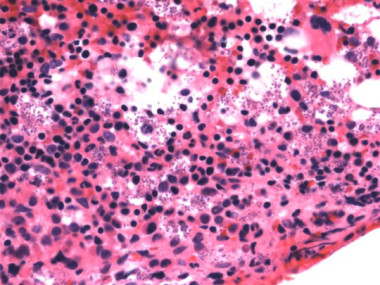

Leishmaniasis Visceral: ~100%